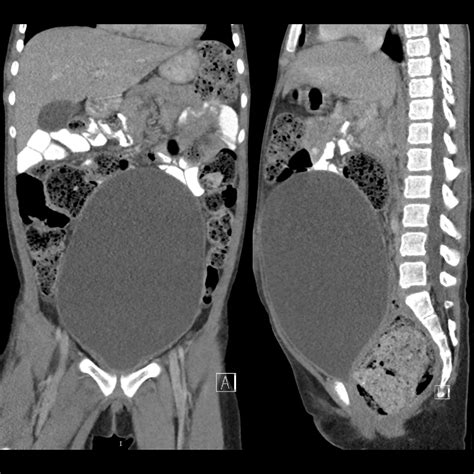

The distension of bladder is a medical condition characterized by the stretching and enlargement of the urinary bladder due to the accumulation of urine that the body cannot naturally expel. While the bladder is designed to be an elastic organ, it has a functional capacity; once that limit is reached or exceeded due to an obstruction or neurological issue, the walls become thin and distended. Understanding this condition is crucial for recognizing the symptoms early, as chronic distension can lead to severe complications, including kidney damage and permanent loss of bladder function.

The physical manifestation of a distended bladder can often be seen and felt as a rounded, firm mass in the lower abdomen, known as a suprapubic mass. Patients often report an uncomfortable sense of fullness, yet they may struggle to initiate urination or maintain a steady stream. In cases of chronic distension of bladder, the patient might experience overflow incontinence, where small amounts of urine leak out because the bladder is simply too full to hold any more.

To confirm the distension of bladder, healthcare providers employ several diagnostic techniques. Physical examination is usually the starting point, where the physician palpates the abdomen to locate the bladder dome. If a large, firm mass is present that disappears after catheterization, the diagnosis is confirmed.